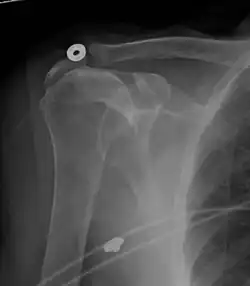

Рентгеновская проекционная рентгенография не может напрямую выявить разрывы вращающей манжеты, «мягких тканей», и, следовательно, обычные рентгеновские лучи не могут исключить повреждение манжеты. Однако косвенные доказательства патологии можно увидеть в случаях, когда одно или несколько сухожилий подверглись дегенеративной кальцификации (кальцифицирующий тендинит). Головка плечевой кости может мигрировать вверх (высоко расположенная головка плечевой кости) вследствие разрыва подостной или комбинированной надостной и подостной мышцами.[44] Миграцию можно измерить расстоянием между:

Обычно первый расположен ниже второго, и поэтому переворот указывает на разрыв вращательной манжеты.[44] Длительный контакт между высоко расположенной головкой плечевой кости и акромионом над ней может привести к обнаружению на рентгеновских снимках износа головки плечевой кости и акромиона или вторичного дегенеративного артрита плечевого сустава, называемого артропатия манжеты.[43] Случайные рентгенологические находки костных шпор в соседнем акромиально-ключичном суставе могут показать костную шпору, растущую от внешнего края ключицы вниз к вращающей манжете. На нижней стороне акромиона также можно увидеть шпоры, которые, как когда-то считали, вызывают прямое истирание вращающей манжеты из-за контактного трения, концепция, которая в настоящее время считается спорной.